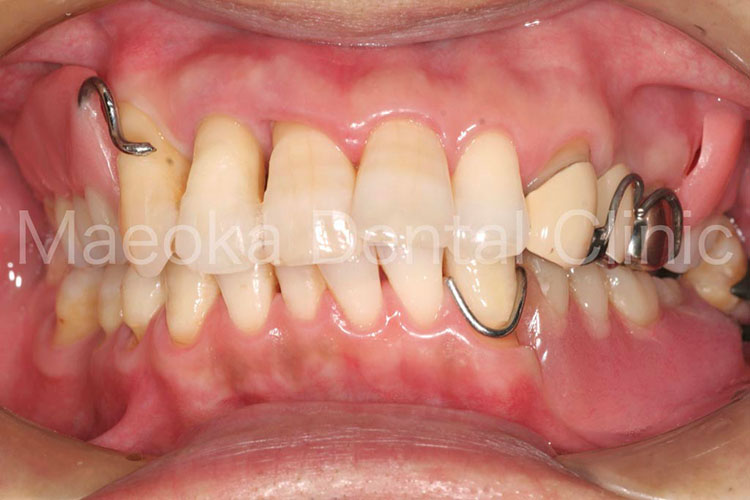

治療前(正面)

治療後(正面)